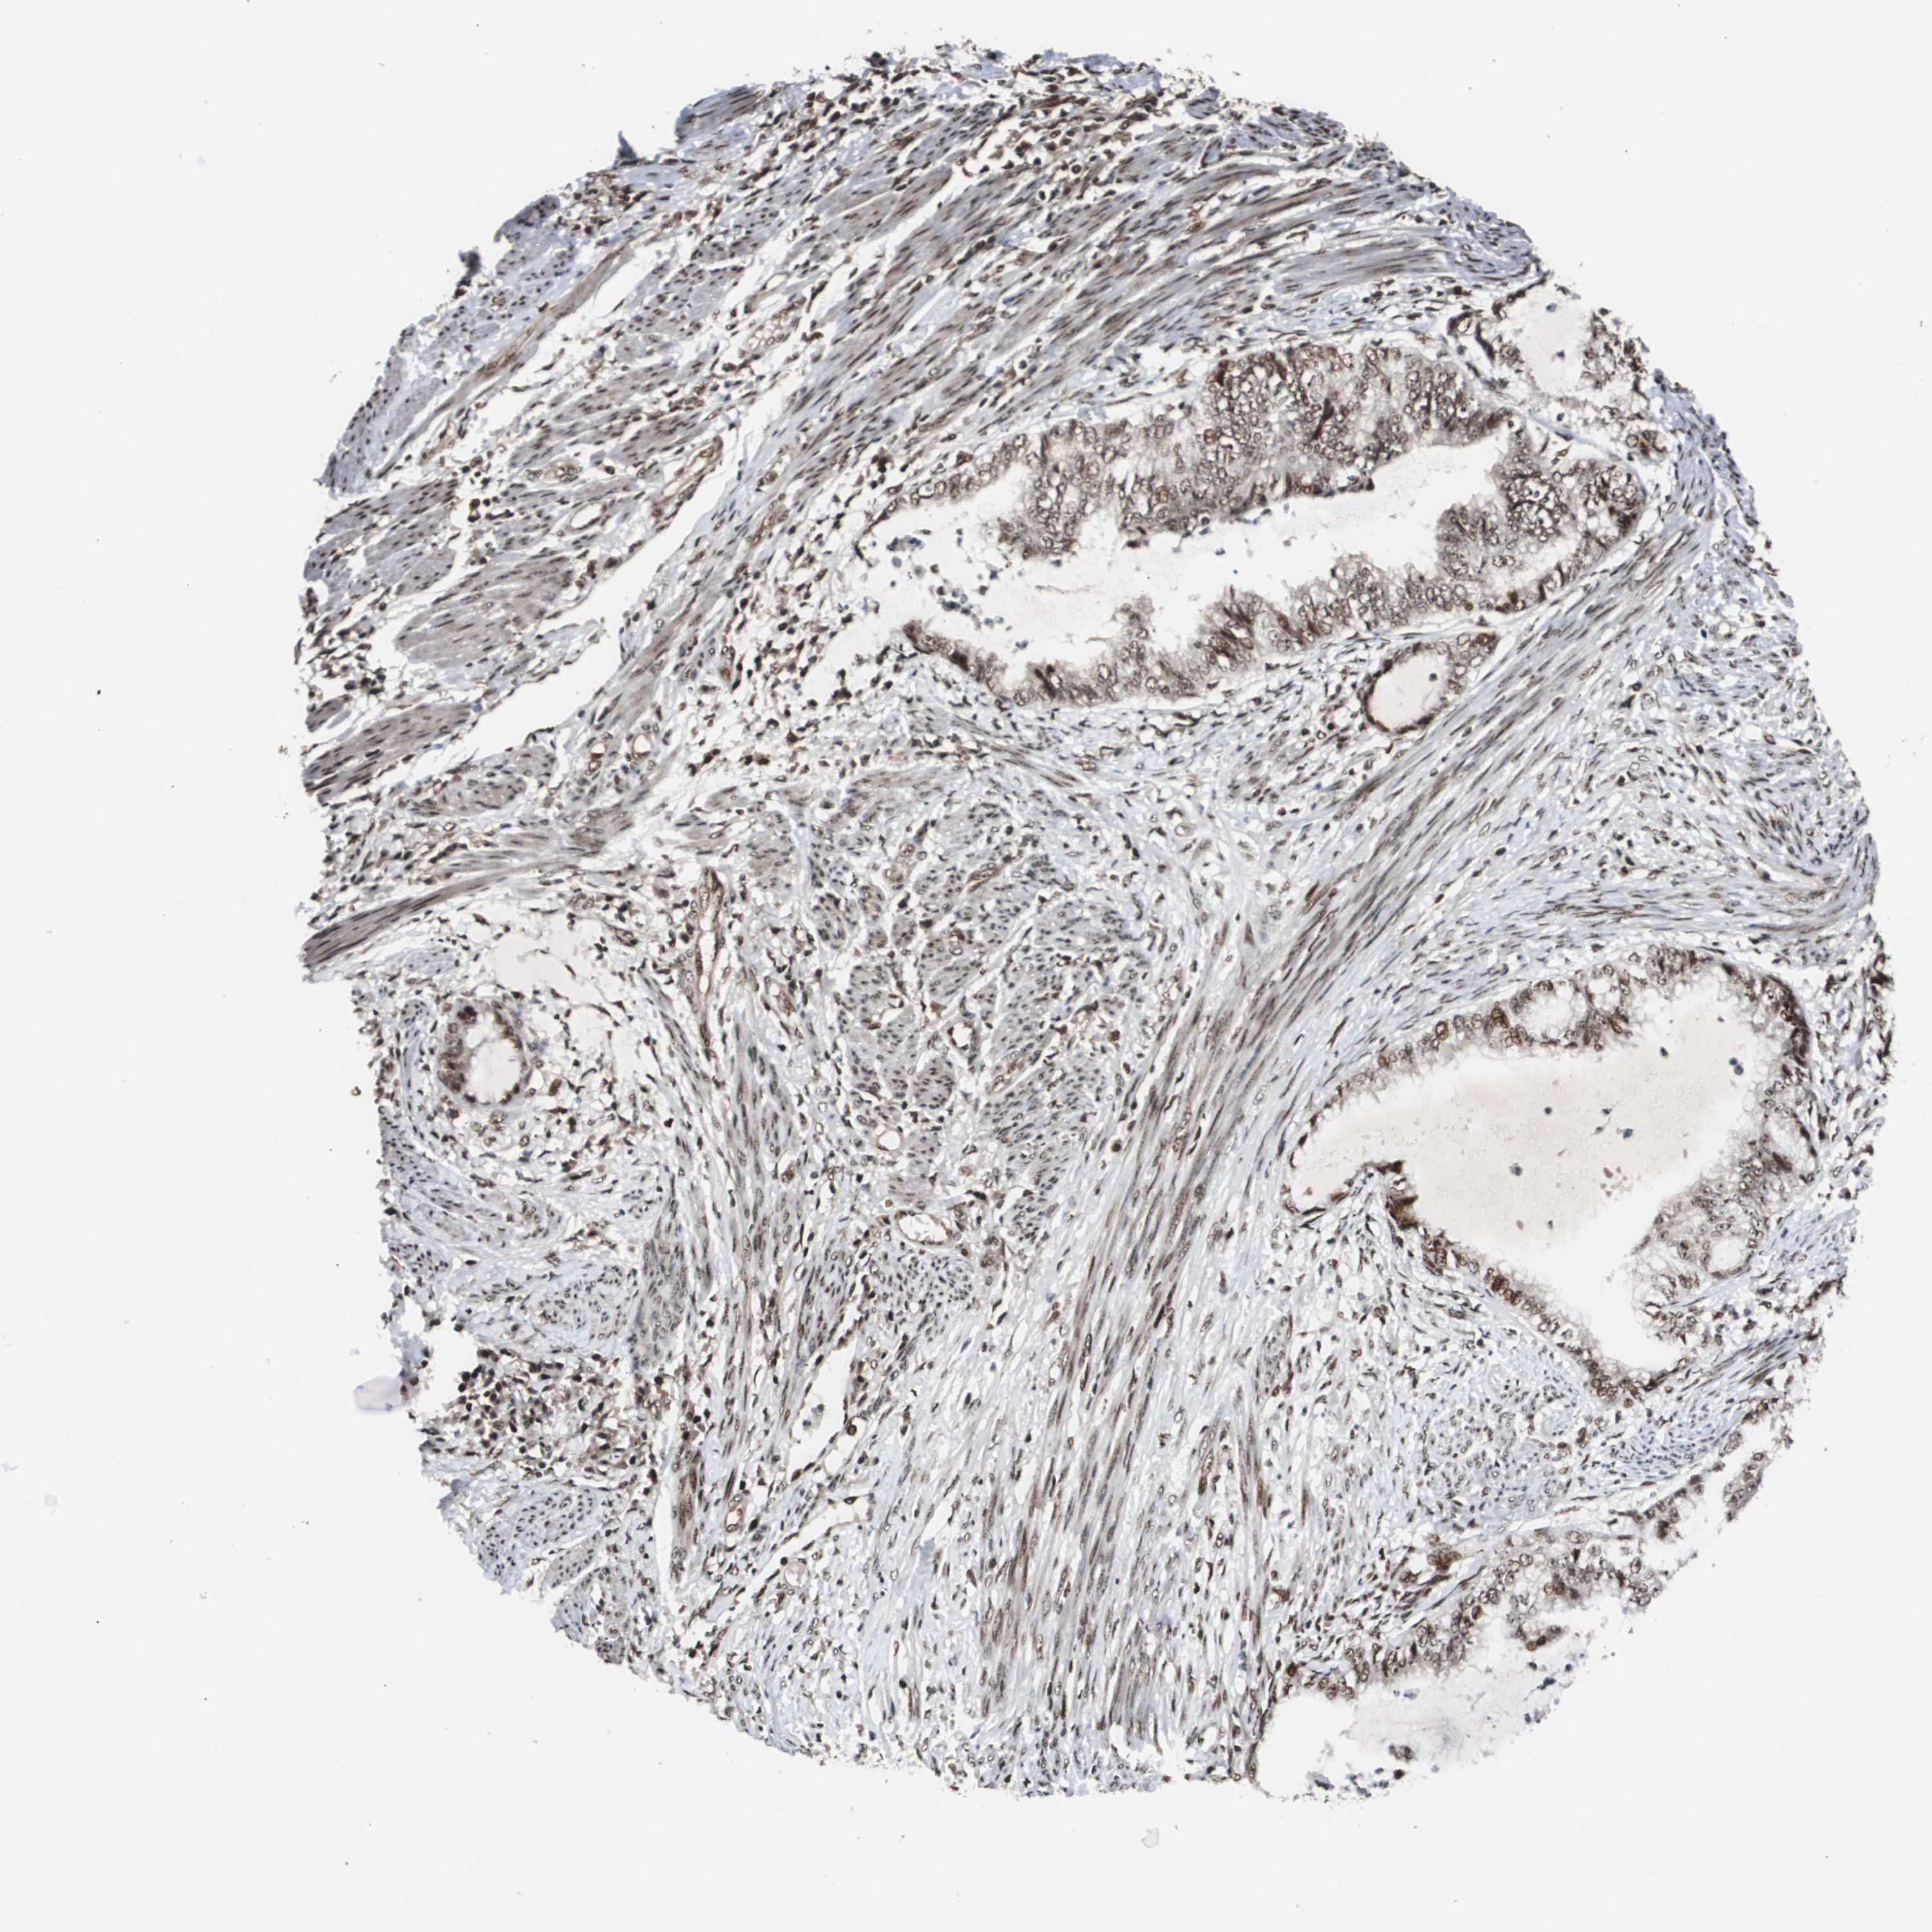

ENDOMETRIAL CANCER - Protein expressioni

A mouse-over function shows sample information and annotation data. Click on an image to view it in a full screen mode. Samples can be filtered based on level of antibody staining by selecting one or several of the following categories: high, medium, low and not detected. The assay and annotation is described here.

Note that samples used for immunohistochemistry by the Human Protein Atlas do not correspond to samples in the TCGA dataset.

Antibody stainingi

Antibody staining in the annotated cell types in the current human tissue is reported as not detected, low, medium, or high, based on conventional immunohistochemistry profiling in selected tissues. This score is based on the combination of the staining intensity and fraction of stained cells.

Each image is clickable and will lead to virtual microscopy that enables deeper exploration of all samples and also displays staining intensity scores, fraction scores and subcellular localization as well as patient and tissue information for each sample.

Antibody HPA006982

Staining

High

Medium

Low

Not detected

Intensity

Strong

Moderate

Weak

Negative

Quantity

>75%

75%-25%

<25%

None

Location

Nuclear

Cytoplasmic/membranous

Cytoplasmic/membranous,nuclear

Adenocarcinoma, NOS